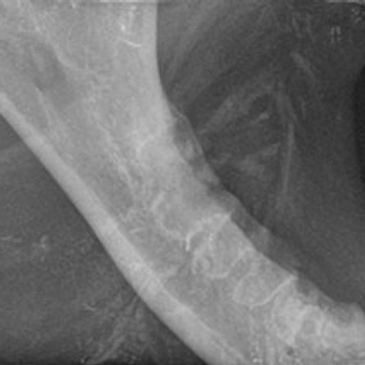

Trauma and advanced periodontal disease are common causes of jaw fractures in canine and feline patients. Jaw fracture stabilization and repair is often performed with wire and acrylic splinting in the mouth. Pets tolerate these appliances well and many owners do not notice them in their pets mouth.